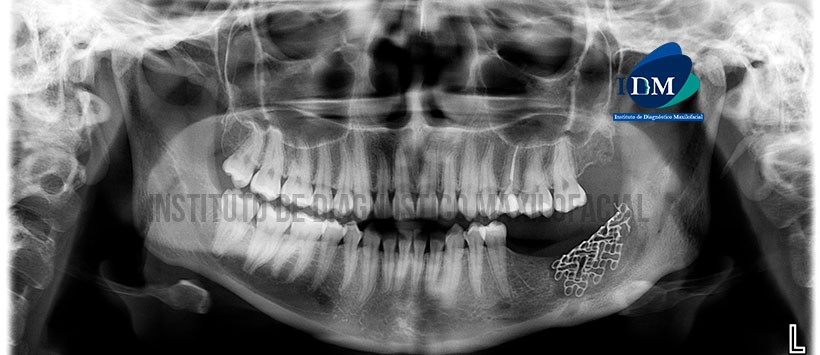

Paciente femenino de 23 años de edad, es referido al Instituto de Diagnóstico Maxilofacial (IDM) para evaluación control tomográfico post quirúrgico de Fibroma Ameloblástico.

En la radiografía panorámica (Figura 1) se observa presencia de malla quirúrgica en zona alveolar del sector postero-inferior del lado izquierdo, asociado a imagen radiolúcida adyacente.

A la evaluación de la tomografía volumétrica (CBCT) cortes axiales (Figura 2), coronales (Figura 3), transaxiales (Figura 4), y tangenciales (Figuras 5), se observa presencia de imagen heterogénea de límites definidos localizado en cuerpo mandibular izquierdo, que se ex tiende en sentido mesio-distal de zona alveolar correspondiente a pieza 37 hacia el borde anterior de la rama y en sentido cefálico-caudal del reborde alveolar hasta el conducto dentario inferior y zona del reborde basal mandibular en su parte mesial. La lesión se encuentra en relación a la presencia de malla quirúrgica y aparentes restos de material de regeneración ósea; ocasiona el borramiento de la cortical superior del conducto dentario inferior y expansión de las tablas óseas vestibular, lingual y reborde basal mandibular con aumento de la densidad ósea circundante.